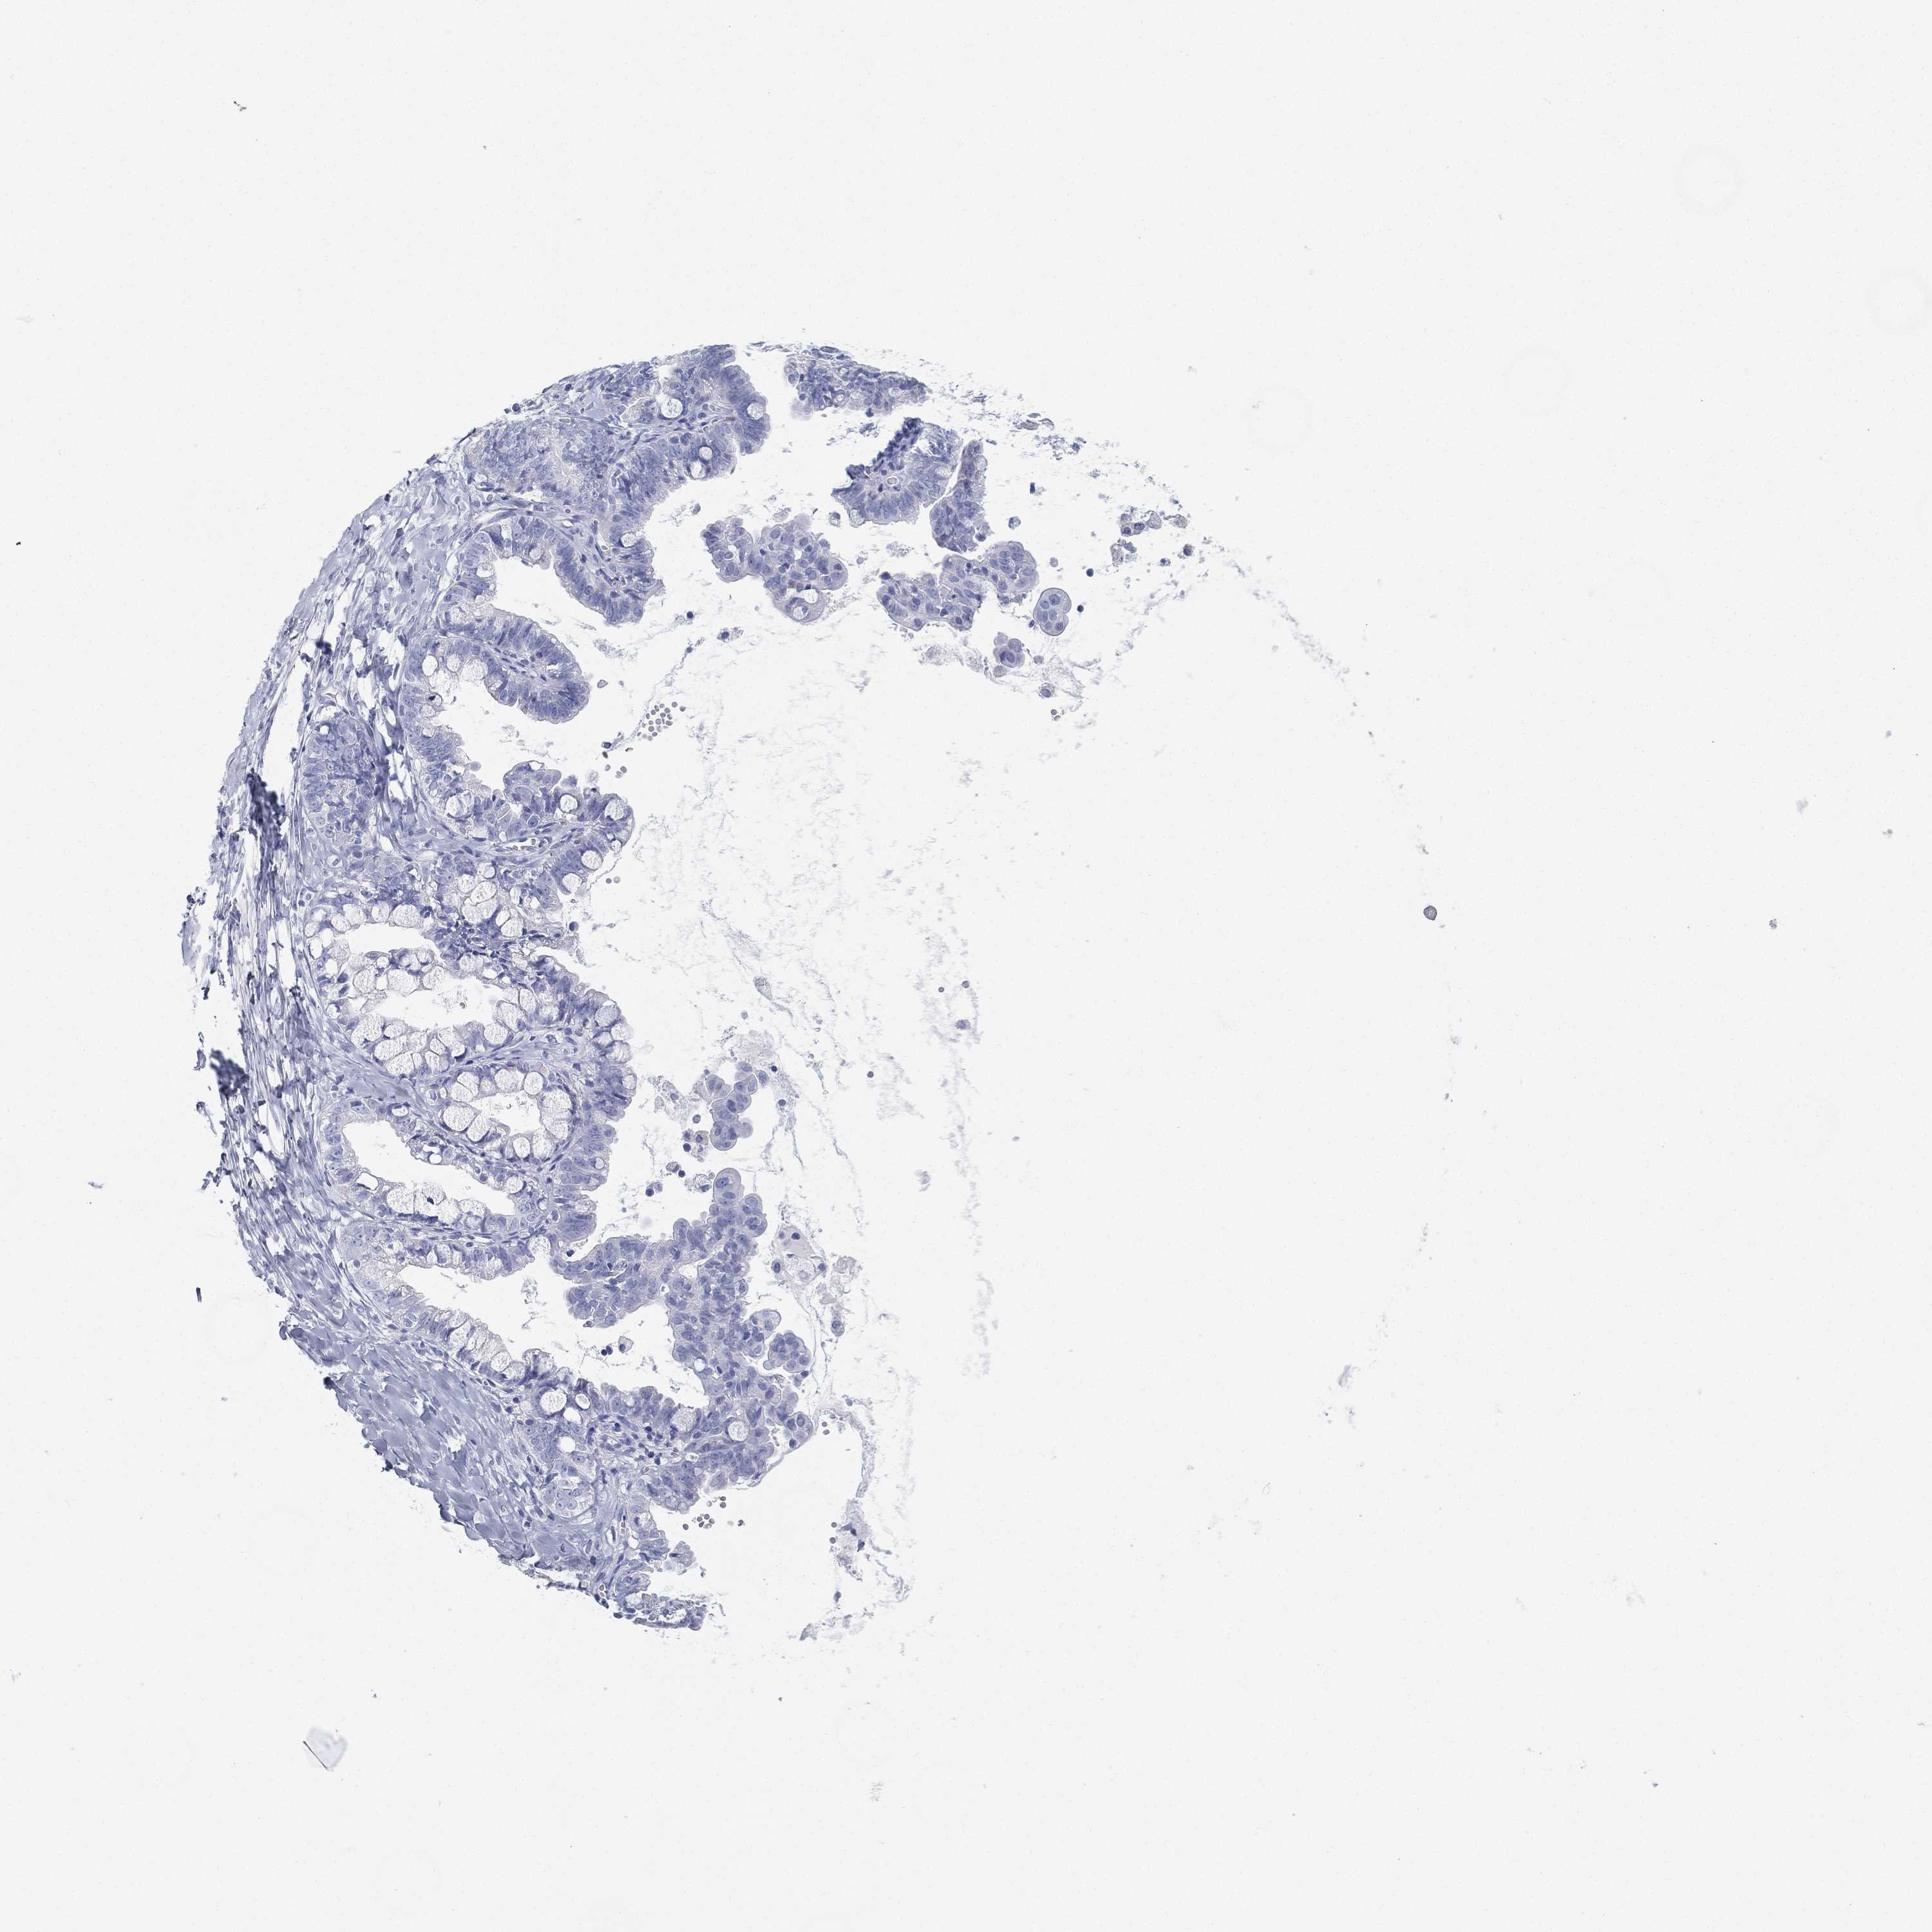

OVARIAN CANCER - Protein expressioni

A mouse-over function shows sample information and annotation data. Click on an image to view it in a full screen mode. Samples can be filtered based on level of antibody staining by selecting one or several of the following categories: high, medium, low and not detected. The assay and annotation is described here.

Note that samples used for immunohistochemistry by the Human Protein Atlas do not correspond to samples in the TCGA dataset.

Antibody stainingi

Antibody staining in the annotated cell types in the current human tissue is reported as not detected, low, medium, or high, based on conventional immunohistochemistry profiling in selected tissues. This score is based on the combination of the staining intensity and fraction of stained cells.

Each image is clickable and will lead to virtual microscopy that enables deeper exploration of all samples and also displays staining intensity scores, fraction scores and subcellular localization as well as patient and tissue information for each sample.

Antibody HPA007326

Antibody HPA026088

Cystadenocarcinoma, serous, NOS

Cystadenocarcinoma, mucinous, NOS

Carcinoma, endometroid